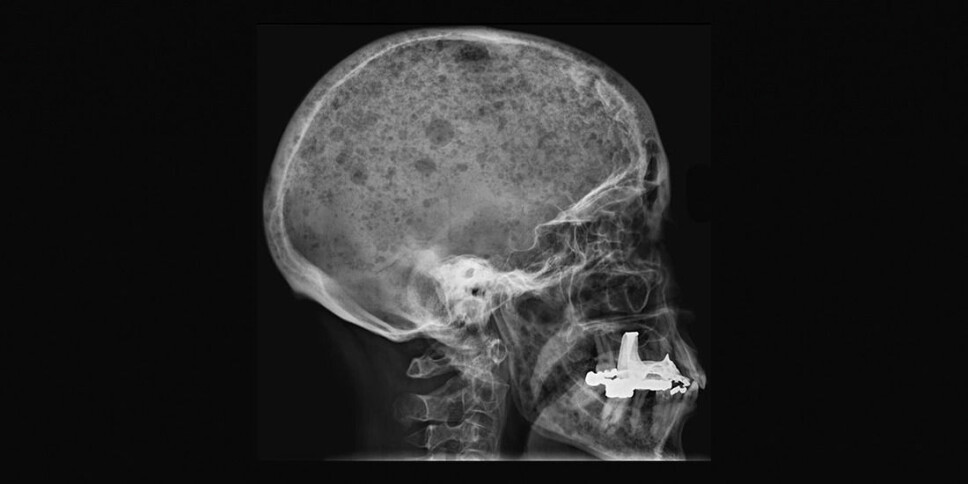

In people with bone marrow cancer, the bone-eating cells run amok. They become too numerous and eat too much. The bone-building gang doesn’t have time to rebuild the bone mass, despite overtime and long shifts. Bone tissue gets gobbled up.

Many people with bone marrow cancer often end up with perforated bones, a condition that is very painful to live with. They sometimes experience collapsed vertebrae or suffer broken bones just by turning in bed.